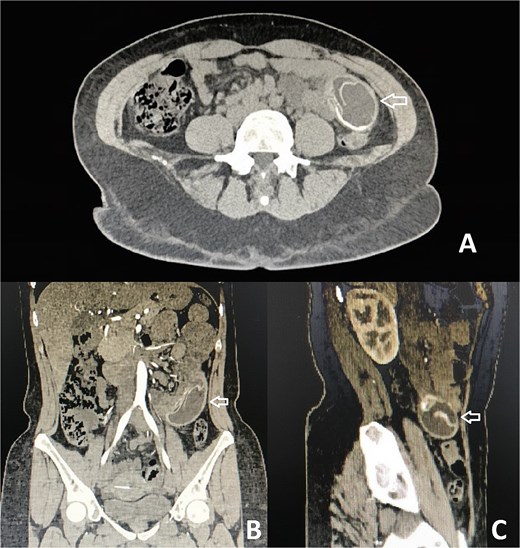

On examination, her abdomen was mildly distended, tender in the right iliac fossa and hypogastrium, with a positive Blumberg sign. Laboratory testing revealed leukocytosis (10 880/mm3) without neutrophilia. Ultrasound findings were unremarkable, but contrast-enhanced computed tomography (CT) demonstrated a foreign body within the jejunum, with proximal small bowel dilatation and a clear transition point—highly suggestive of gastric balloon migration and obstruction (Fig. 1).

CT with evidence of a foreign body compatible with a migrated gastric balloon (indicated by the arrow). (A) Axial plane. (B) Coronal plane. (C) Sagittal plane.